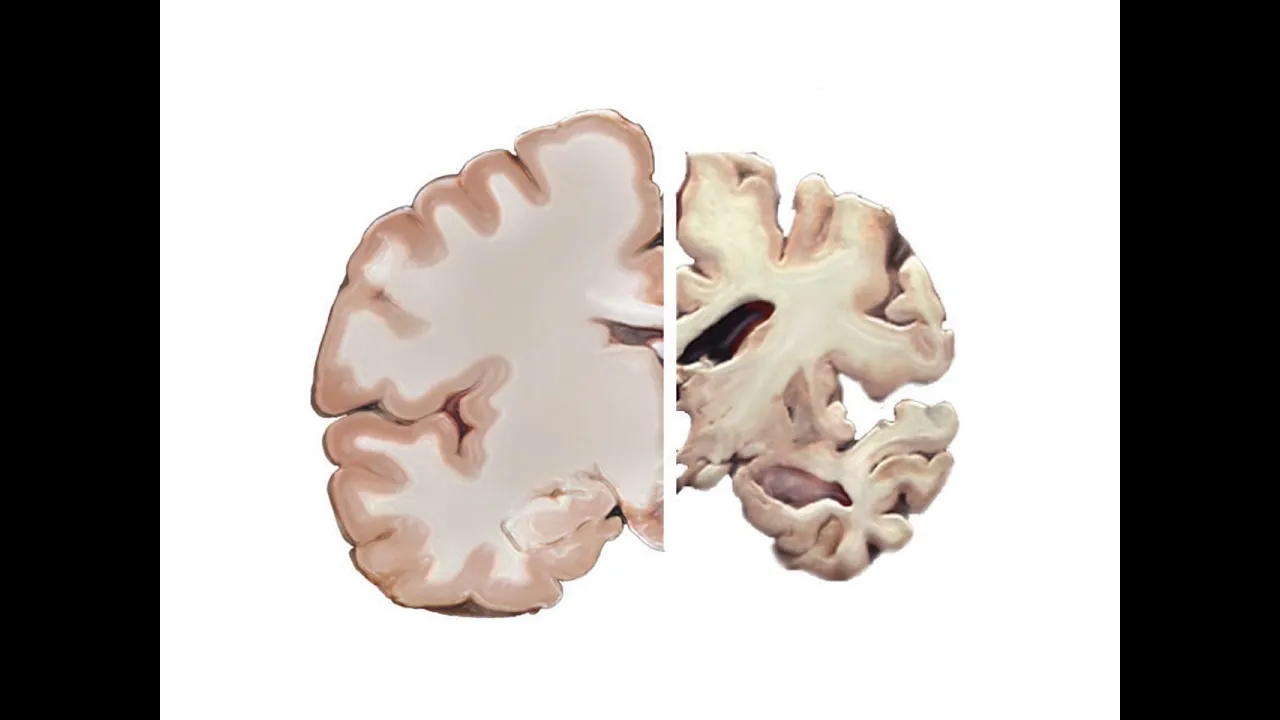

dementia cases are Alzheimer's the disease is associated with the accumulation of plaques and tangles in the brain changes accompanied by damage to brain cells and their death the older a person is the more likely they are to have developed Alzheimer's but Alzheimer's is not a part of normal aging symptoms of Alzheimer's disease include a decrease in the ability to think and remember confusion about time and place new difficulties speaking and writing changes in mood and personality as we fight against other diseases and live longer lives Alzheimer's looms on the horizon as if waiting for us

deaths what we do know is that Alzheimer's disease is associated with these plaques in the brain as well as another protein related anomaly tangles a protein called tau stabilizes microtubules in brain cells like railroad ties holding tracks together the tracks that guide nutrients and other molecules throughout the cell in many neurodegenerative diseases tau proteins become abnormally sticky and tangled with other tau proteins compromising the delivery network we do know some factors associated with increased or decreased risk but their exact relationships with cognitive decline aren't all certain things associated with a reduced risk for Alzheimer's disease